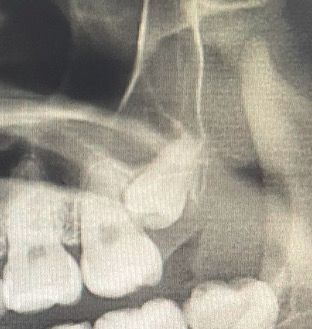

위쪽 어금니 옆 사랑니 방향이 너무 뿌리쪽으로 치우쳐서 그런데

치근 흡수 가능성이 있을까요??

치근을 흡수할 가능성이 있으나 정확한 진단은 3d 촬영이 필요하며 뽑는 것이 좋아보입니다.

사진으로만 봤을 경우에는 뿌리를 흡수할 가능성이 높아 보이진 않습니다. 하지만 매복된 치아의 경우에는 드문 확률로 인접체 뿌리를 녹이는 경우도 있기 때문에 정확한 확인을 위해서는 주기적으로 치과에서 검진을 받아보는 것이 좋습니다.

파노라마 상으로는 앞쪽 치아에 걸려있어 치근 흡수와 염증 및 충치발생 가능성은 있습니다. 다만 파노라마는 상이 중첩되어보이기 때문에 정확한 3차원적 관계를 보기 위해서는 ct를 찍어보아야 알 수 있습니다.

사랑니가 옆의 어금니와 인접하기 때문에 치근흡수 및 충치유발 가능성이 다소 있는 상태입니다